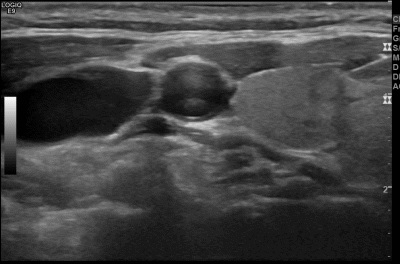

상기환자  갑상선 양성 추정결절  추적관찰차 내원하신 60대중반 여성분으로 의심스러운 갑상선 우엽 결절 세포검사진행후 갑상선암으로 진단되었습니다